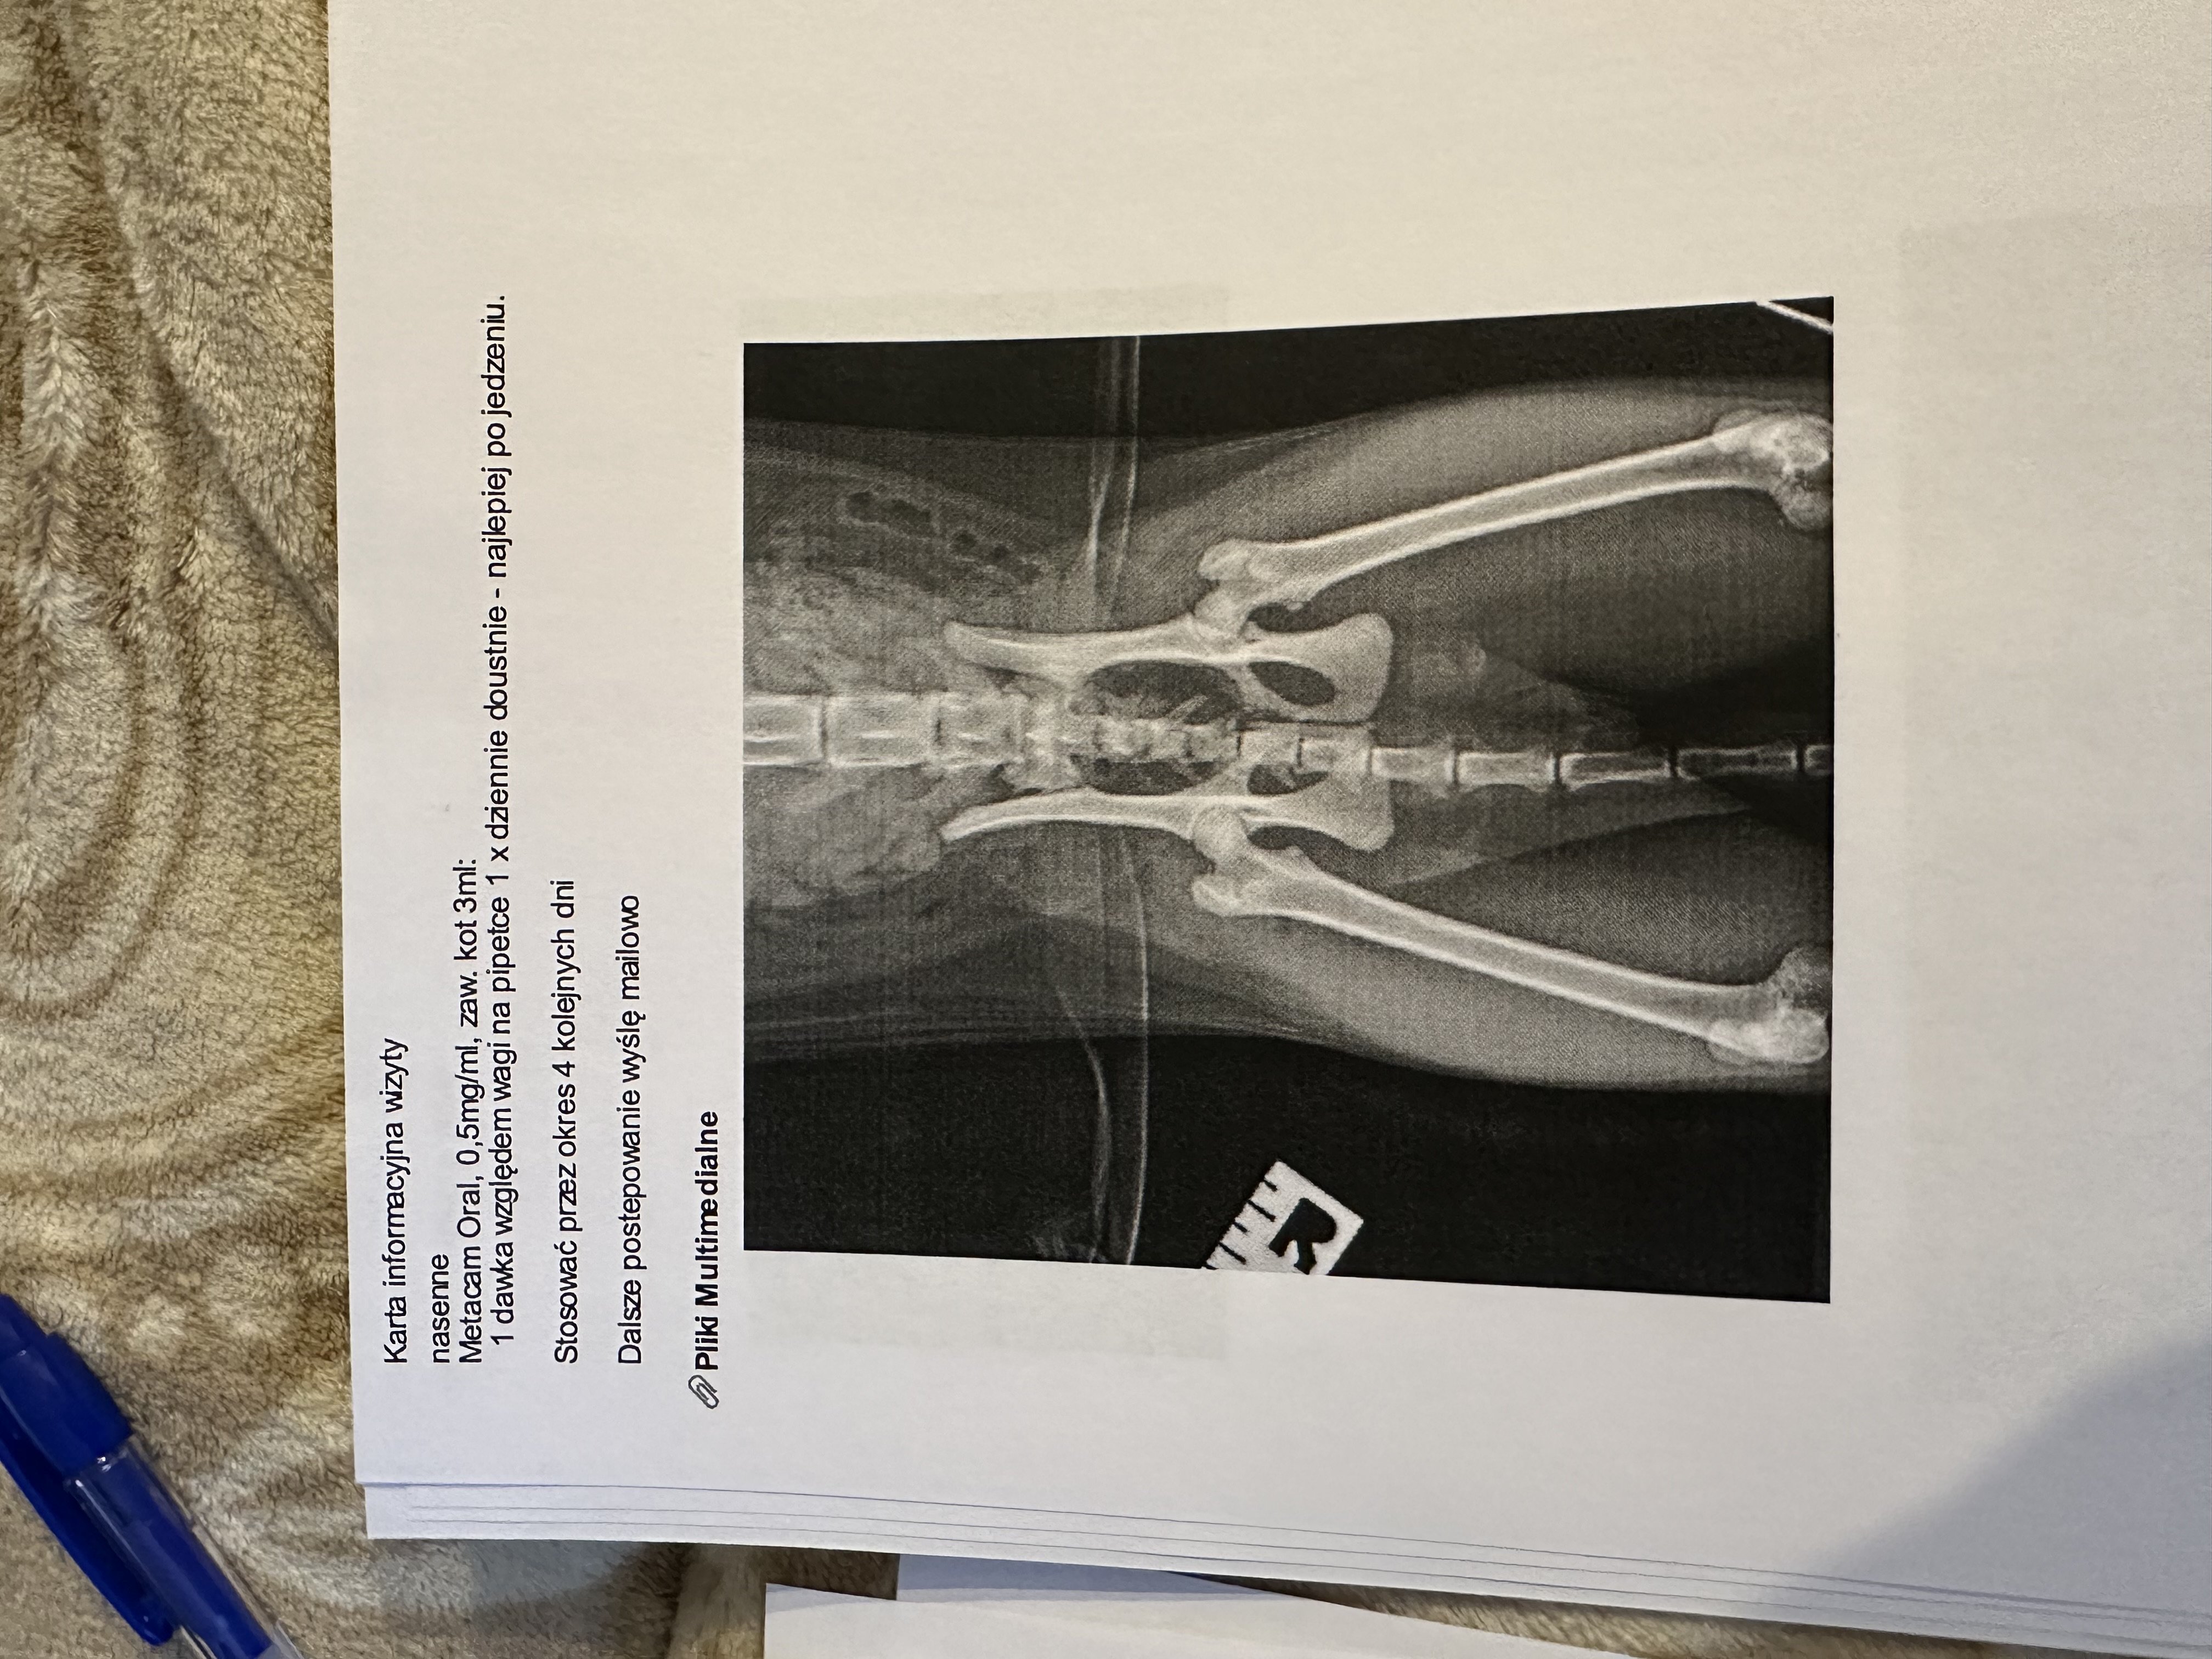

Kolejna konsultacja miała miejsce w innej klinice, gdzie lekarze nadal podejrzewali problemy ortopedyczne, dlatego przeszedł szczegółowe badania, w tym RTG kręgosłupa i bioder i konsultacje specjalistyczną. Wdrożono leczenie Gabapentyną oraz Metacamem, aby zmniejszyć ból i uspokoić kota. Zalecono dalszą obserwację oraz ewentualne kolejne badania, jeśli objawy nie ustąpią.

Badania ortopedyczne oraz biochemia wraz z morfologią nie wykazały poważnych zmian (lekarza poinformował, aby nie decydować się na badanie TK/MRI, ponieważ podłoże problemu leży gdzieś indziej; a z USG się wstrzymać).